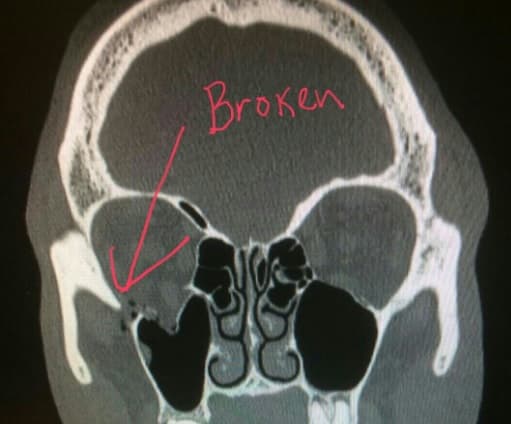

LONDRES – Kell Brook probó el poder de Gennady Golovkin y la consecuencia fue la fractura del orbital derecho del ojo.

Kell Brook con el orbital del ojo roto, Golovkin se lo quebró

Eddie Hearn promotor del británico confirmó la lesión.

“Gracias a todos por sus mensajes. Kell tiene roto el orbital del ojo”, escribió en twitter.